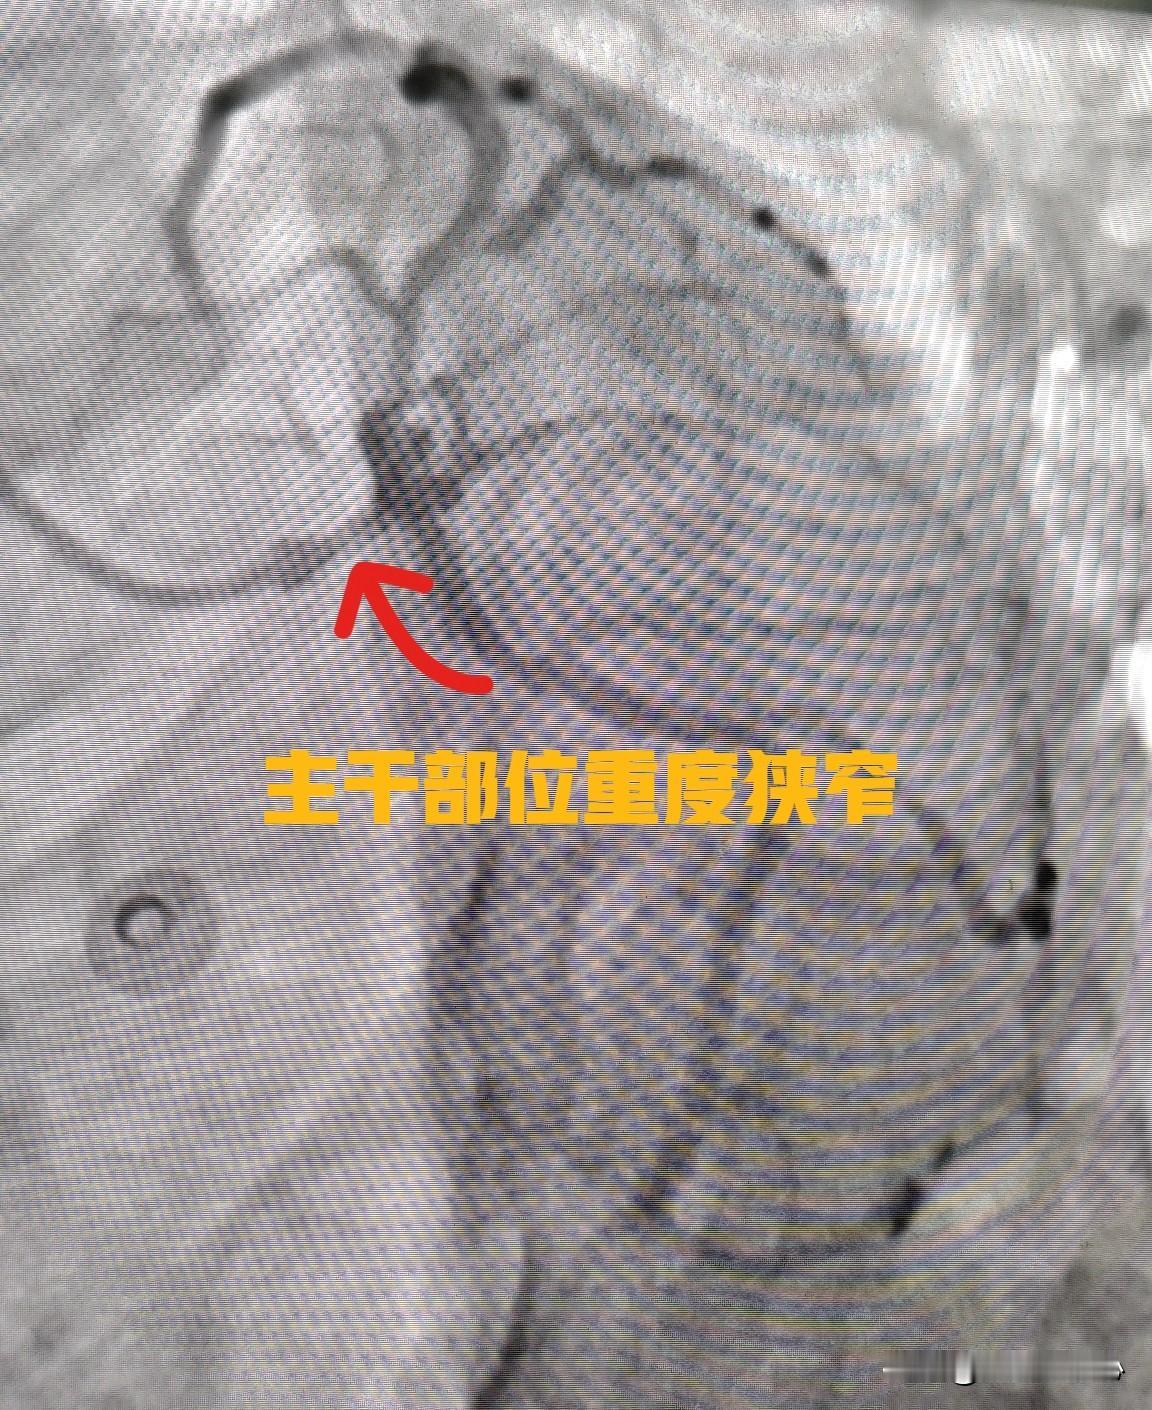

78 岁老人冠心病药物保守治疗。今天给一个78岁老年女性的冠心病患者做了心脏造影。造影显示前降支有大约 80% 狭窄,伴有严重的钙化。询问患者是否有冠心病、心绞痛的症状。回答说不明显,偶有胸闷症状。考虑到患者高龄,合并钙化、扭曲,斑块目前还是挺稳定的,一般不会突然破裂导致急性心梗,最终选择了药物保守治疗。